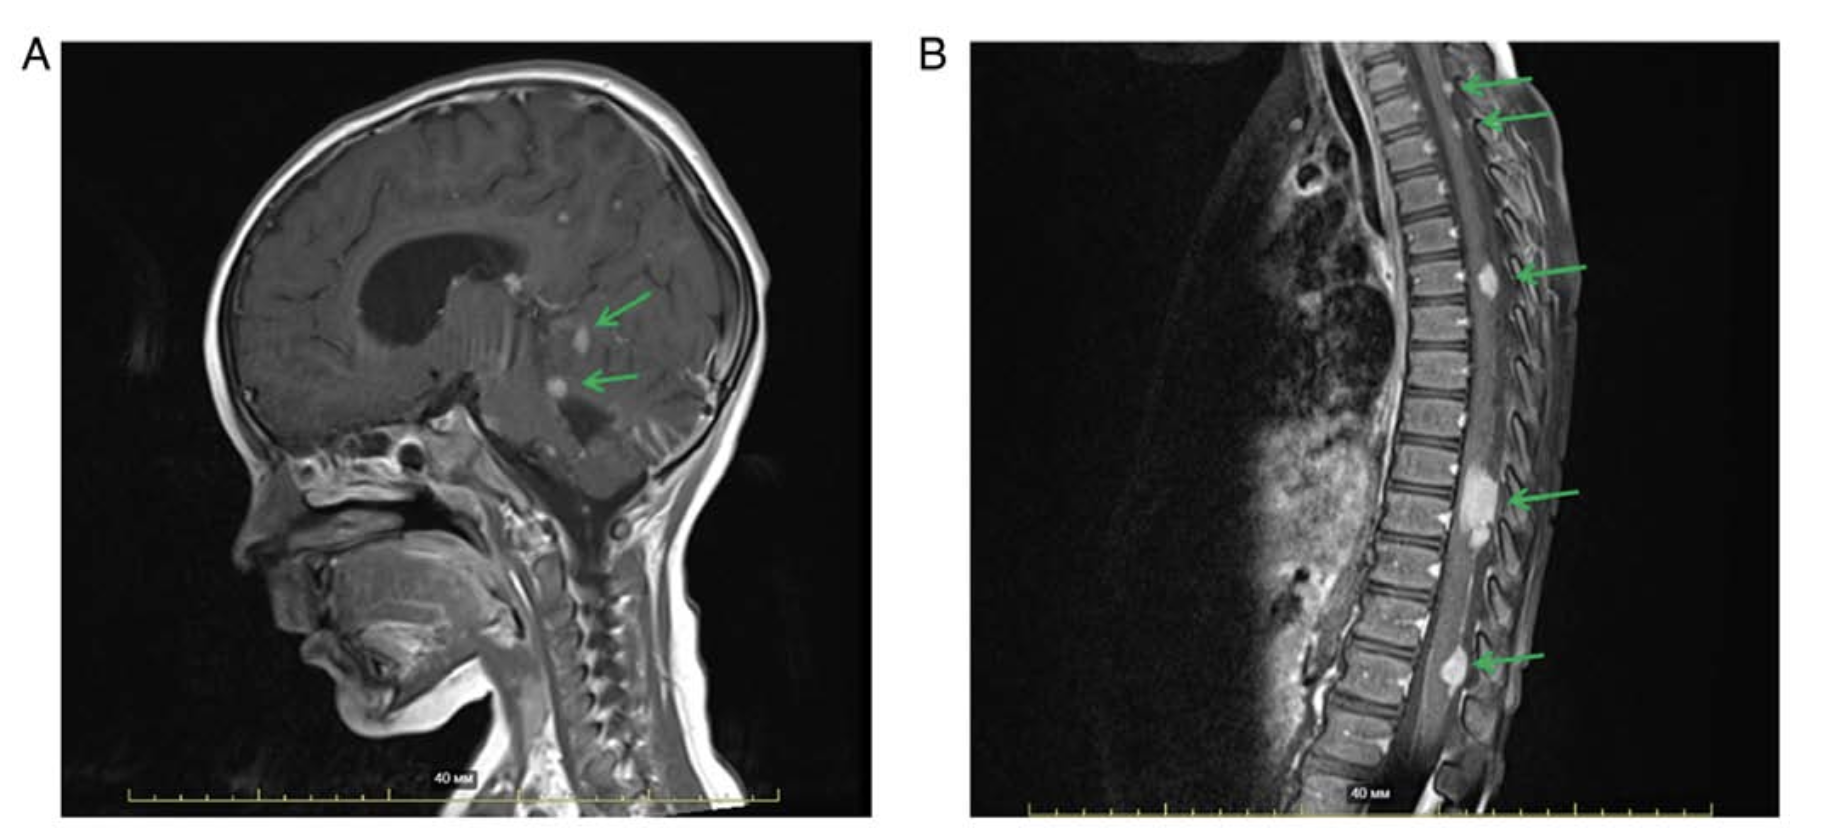

Medulloblastoma (MB) is one of the most common pediatric malignant tumors arising from the central nervous system with an unknown etiology and variable prognosis. Relapsed or refractory MB in pediatric patients after intensive anticancer therapy (chemo‑, radiotherapy) is associated with treatment resistance and poor survival prognosis. Metronomic chemotherapy in combination with mTOR inhibitors may have advantages due to an alternate mechanism of cytotoxicity and a favourable adverse effects profile. Furthermore, it is considered to be a prospective anticancer regimen regardless of the presence/absence of molecular targets. The present study reported a successful result of this treatment option with optimal tolerability in relapsed MB in a pediatric male patient and highlighted the advantages for a selected group of patients.